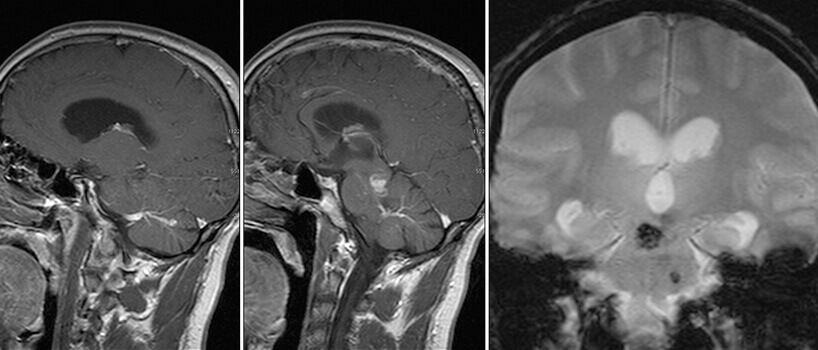

Είναι καλοήθεις δυσπλασίες στο φλεβικό σκέλος, με σηραγγώδεις φλεβικές λιμνάσεις, χωρίς αρτηριοφλεβώδη επικοινωνία. Μπορεί να είναι μονήρεις (σποραδική μορφή) ή πολλαπλές. Στην τελευταία περίπτωση είναι συνήθως οικογενείς και κληρονομούνται κατά τον αυτοσωματικό επικρατούντα χαρακτήρα (χρωμόσωματα 7q21-22(CCM1), 7p13-15(CCM2) και 3q25-27(CCM3)).

Αυξάνονται σε μέγεθος μετά από επεισόδια αιμορραγίας λόγω υποτροπιαζόντων, συρρρεόντων μικροαιματωμάτων που συμβαίνουν σε διαφορετικές χρονικές περιόδους. Εντός της βλάβης διακρίνονται αιμορραγικά στοιχεία σε διαφορετικά χρονικά στάδια (παλαιότερα και πιό πρόσφατα).